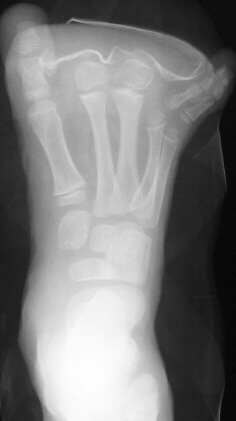

at age 5 years, she underwent partial amputation of the right

2nd and 3rd metatarsals(images 3 & 4). Now at age 10, she

has been doing well, participating in all sports. She has noted

that there has been some difficulty in finding shoes that fit,

but does not complain of any pain.